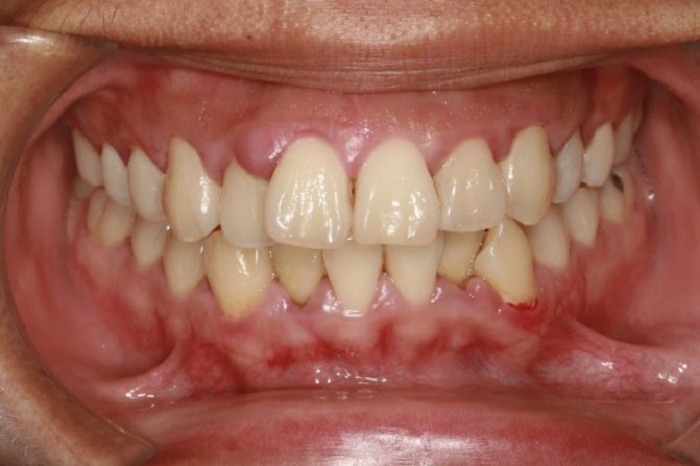

Viêm nha chu

Đây là bệnh lý hay gặp hàng đầu về răng miệng. Vi khuẩn xâm nhập và phát triển trên các mảng bám răng là nguyên nhân gây viêm nha chu. Mảng bám dần dày lên, tích tụ trên thân răng cùng với số lượng vi khuẩn ngày càng nhiều nếu bạn không vệ sinh răng sạch sẽ.

Các triệu chứng của viêm nha chu như chảy máu chân răng, hơi thở có mùi hôi, có cảm giác đau khi nhai, răng dễ bị lung lay,…Nếu để kéo dài, không có biện pháp chữa trị kịp thời, có thể dẫn đến mất răng hay mắc các bệnh về đường hô hấp, viêm khớp dạng thấp, đột quỵ,…